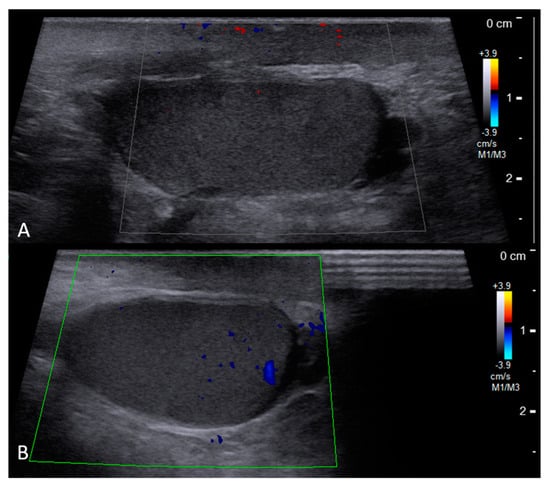

2. Case Report